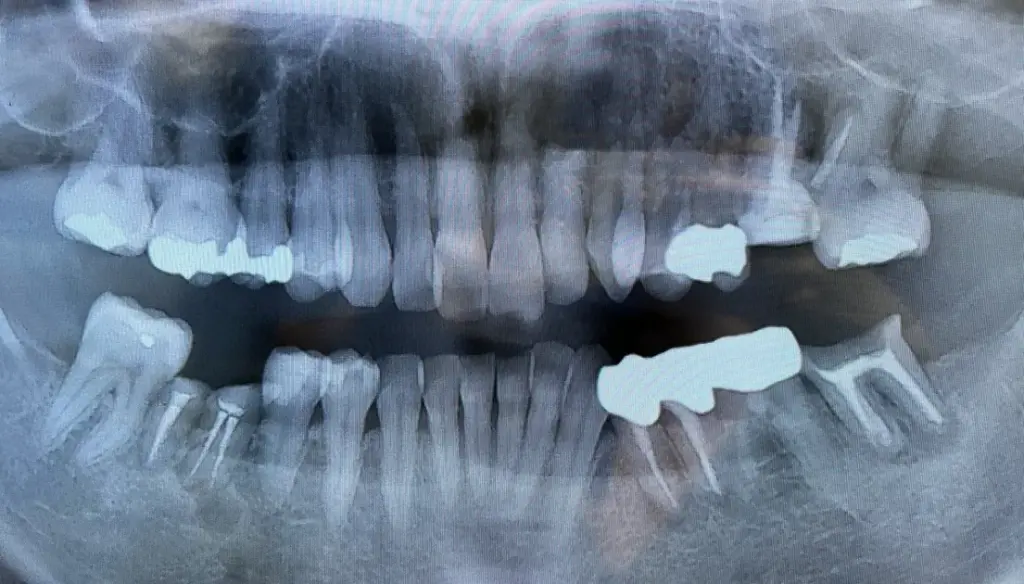

親知らずは、通常17歳から25歳の間に生えてくる第三大臼歯です。

この歯は、前の大臼歯に続く最後の歯であり、口腔内の一番奥に位置しています。